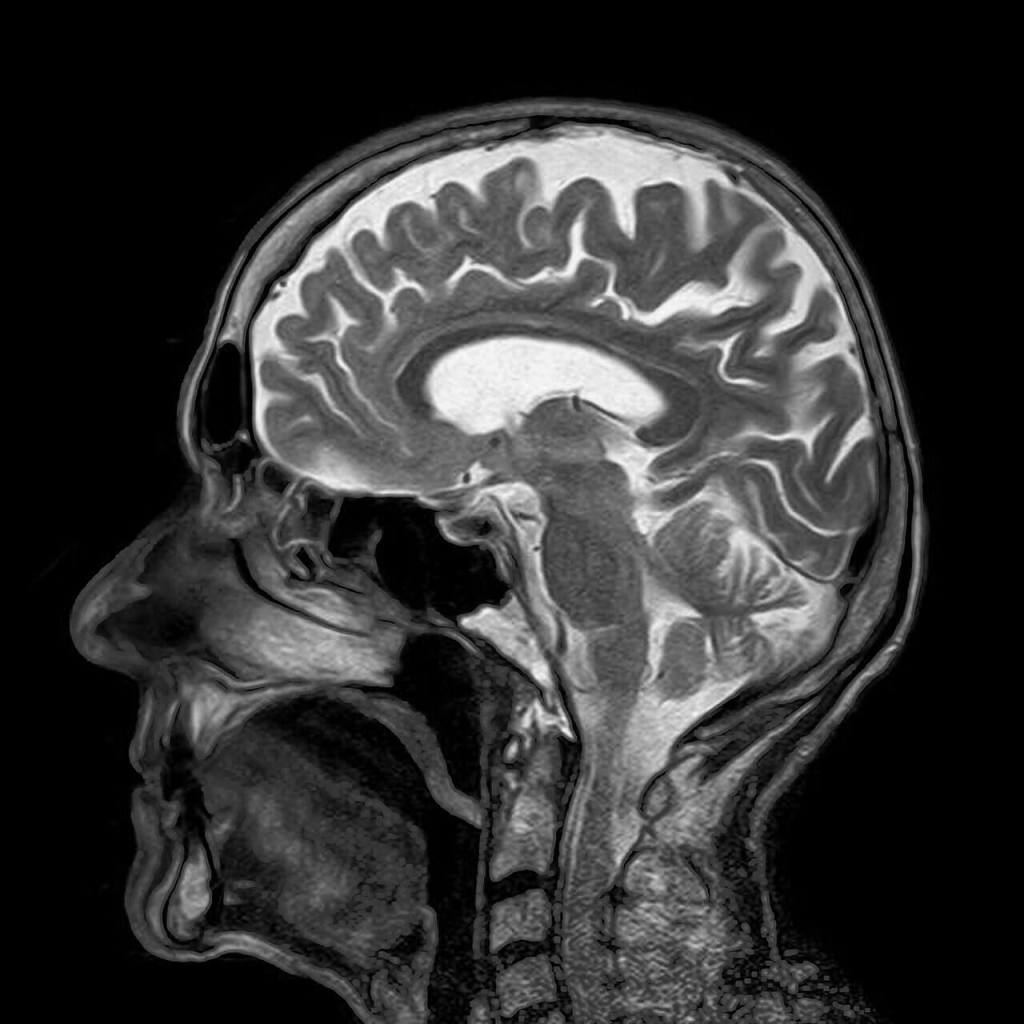

Osnabrück es una hermosa ciudad alemana de Baja Sajonia, famosa por acoger la firma de la Paz de Westfalia que puso fin a la guerra de los 30 años. Visité la ciudad por primera vez en diciembre de 2005, coincidiendo con el tradicional mercado navideño de la ciudad, invitado a participar en un seminario organizado en la Universidad de Osnabrück. La universidad me alojó en el conocido hotel Walhalla, que se enorgullecía de aparecer reflejado en una de las obras del famoso escritor Erich Maria Remarque, natural de Osnabrück y autor de la gran novela pacifista Sin novedad en el frente. Al llegar al hotel coincidí con otro de los participantes en el seminario, el profesor Ian R. Young, un físico británico de gesto muy adusto, profesor de radiología en el Imperial College of Science, Technology and Medicine de Londres. Entonces no lo sabía, pero el profesor Young era todo un pionero de la ciencia, había sido el artífice de la obtención por primera vez en la historia de la imagen por resonancia magnética de un cerebro humano en 1978. Más de cuarenta años después de ese gran logro, la técnica de imagen médica por resonancia magnética se ha convertido en una de las más valiosas herramientas de diagnóstico médico de que disponemos hoy en día, y al igual que sucede con otros muchos avances tecnológicos de los que disfrutamos, sus fundamentos físicos se basan en un fenómeno de naturaleza cuántica.

La RMN es una de las principales técnicas de obtención de imagen médica junto con la ecografía por ultrasonidos, la tomografía axial computarizada, o TAC, y la tomografía por emisión de positrones, o PET, por sus siglas en inglés (Positron Emission Tomography). De entre todas estas técnicas, la RMN y la TAC son las que ofrecen mejor resolución de imagen (hasta un milímetro), aunque en la imagen de TAC se realzan los tejidos duros, como el hueso, mientras que en la RMN el contraste se produce para los tejidos blandos. La principal diferencia entre ambas técnicas es que en la TAC se hace uso de radiaciones ionizantes (rayos X) y, en cambio, en la RMN se emplea radiofrecuencia, que es una radiación no ionizante, lo que hace que la RMN carezca de los riesgos asociados a exposiciones prolongadas que sí presenta la TAC. No obstante, la RMN presenta ciertos inconvenientes frete a la TAC. Los principales son el intenso ruido que genera el sistema, que puede resultar incómodo para el paciente, y un intervalo de tiempo mayor para la exploración y la adquisición de las imágenes, de decenas de minutos o incluso una hora en el caso de la RMN frente a solo algunos minutos en el caso de la TAC. Además de esto, la exploración por RMN puede producir claustrofobia en algunos pacientes debido a que el cilindro hueco en el que deben introducirse suele ser de mayor longitud que el del escáner de TAC. Algunos escáneres de RMN tratan de resolver este último inconveniente mediante el uso de una estructura abierta en forma de U que reemplaza al tubo, pero la calidad de la imagen en este tipo de escáneres es inferior.

La imagen médica por RMN se basa en el fenómeno de la RMN para el núcleo más abundante en el organismo humano, el núcleo de hidrógeno, ya que casi el 70 % de la masa de un cuerpo humano es agua y hay dos núcleos de hidrógeno en cada molécula de agua. La imagen médica por RMN es una técnica altamente sofisticada que combina el uso de sistemas de emisión de ondas de radiofrecuencia de gran potencia (del orden del kW) y de detección de señales de radiofrecuencia extremadamente débiles (las producidas por los núcleos de hidrógeno de los tejidos del paciente), con el uso de campos magnéticos estáticos muy intensos, desde 0,2 hasta 7 Teslas en aplicaciones clínicas, e incluso 9,4 Teslas en investigación en humanos y hasta 17,6 Teslas en el caso de animales. En el caso de aplicaciones clínicas en humanos los sistemas de 1,5 y 3 Teslas son los más extendidos (un campo magnético de 3 Teslas es en comparación 60 000 veces más intenso que el campo magnético terrestre promedio).